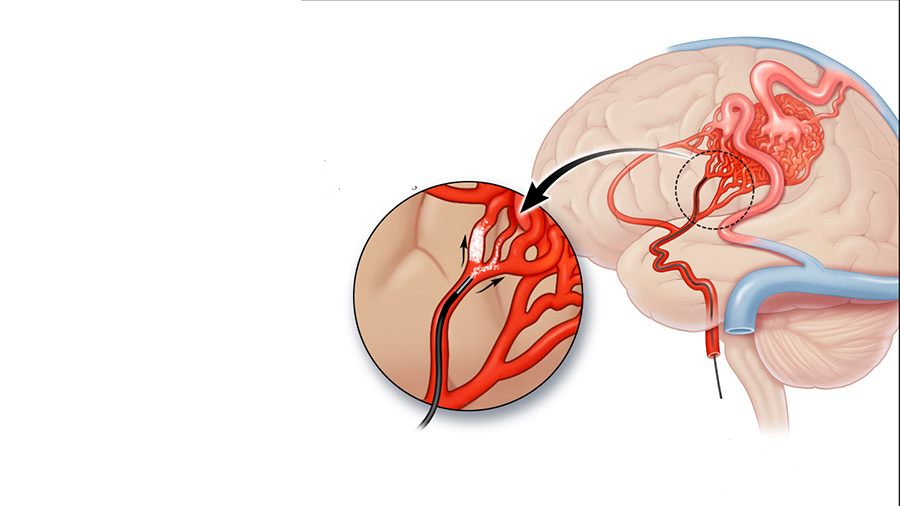

Με ελάχιστα παρεμβατικές μεθόδους, χωρίς ανοιχτό χειρουργείο, ξεκινώντας από τη μηριαία αρτηρία και πλοηγώντας καθετήρες (σωλήνες) και μικροκαθετήρες, με τη βοήθεια μηχανήματος παραγωγής ακτίνων Χ, φτάνουμε στο επίπεδο της βλάβης, που βρίσκεται τις περισσότερες φορές εντός του εγκεφάλου. Εκεί με μία ποικιλία υλικών, που έχουμε στη διάθεσή μας, μπορούμε να απομονώσουμε μια παθολογική επικοινωνία, να αποφράξουμε ένα ανεύρυσμα, να διανοίξουμε ένα αποφραγμένο αγγείο. Η επέμβαση γίνεται με γενική αναισθησία και τις περισσότερες φορές χρειάζεται μικρής διάρκεια νοσηλεία. Η αποκατάσταση είναι σύντομη και ο ασθενής επιστρέφει στην καθημερινή ζωή του χωρίς να υπάρχει πλέον το αιμορραγικό ρίσκο.

Ενδαγγειακά, με τεχνική μέσω των αρτηριών ή και των φλεβών με μικροσωλήνες φτάνουμε έως το σημείο της παθολογίας και με ειδικό υγρό εμβολικό υλικό αποφράσσουμε την παθολογία.